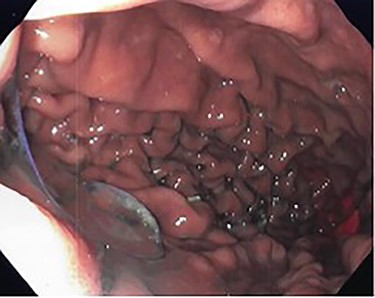

She underwent an upper gastrointestinal series that showed a normal-appearing stomach without any evidence of her prior gastroplasty, moderately sized hiatal hernia and slight delay in passage of contrast through the gastroesophageal junction (Fig. 1). On subsequent endoscopy, she was noted to have multiple loosely placed sutures within the gastric lumen along the greater curvature (Fig. 2), as well as a large-sized paraesophageal hernia.

Barium swallow showing hiatal hernia postendoscopic gastroplasty.